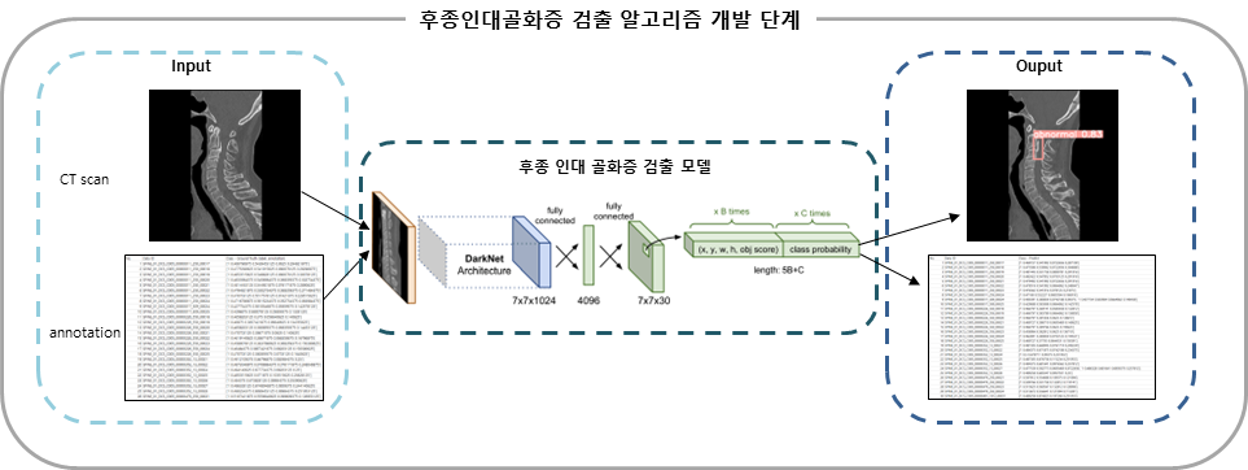

AI 모델 상세 설명서 다운로드1. 후종인대골화증 검출 알고리즘

- 모델 학습

- 데이터는 입력 CT 영상과 골화증 영역을 가리키는 annotation 지표를 사용. 특징 추출 모델로 사용된 YOLO는 하나의 convolutional network가 한 번에 여러개의 영상 내 영역을 예측해내고, class probability를 single regression을 통해 분석. 모델 내 복잡한 파이프라인이 없어 학습 속도가 빠르며, 전체 이미지를 보고 결과를 추정하기 때문에 class에 대한 맥락적 이해도가 높고, R-CNN 계열 모델보다 검출 성능이 높다고 보고됨.

1. 후종인대골화증 검출 알고리즘 모델 학습 학습(Training) 검증(Validation) 시험(Test) 개요 – YOLO사용 – 학습도중 모델의 성능 평가 – 학습 이후 모델의 성능평가

– PR Curve 등데이터 비율 648장(60%) 216장(20%) 216장(20%)